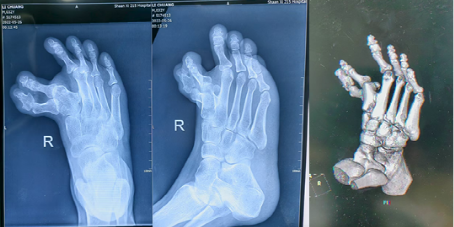

术前影像

二一五医院足踝外科宋强主任团队接诊后,为李先生进行了系统评估。诊断结果远比单一的“多趾”复杂,右足先天性拇内翻、多趾畸形、并发的第2、3趾内翻,以及最关键的第一、二跖骨间存在“骨桥”。两根本该独立活动的脚部骨骼,被一根多长出来的骨头强行连接在一起,严重限制了骨骼的正常复位,是导致手术复杂的关键所在。